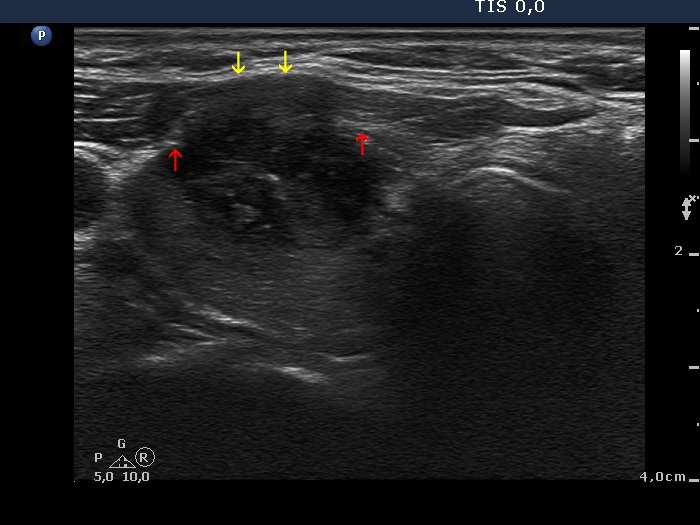

The borders of the nodule - case conp 060 (ultrasonographic picture 1b)

Right lobe, transverse scan. Red arrows point to the most ventral part of the lobe outside the nodule while yellow arrows do to the most ventral part of the tumor. The difference means an unusually large degree of bulging.